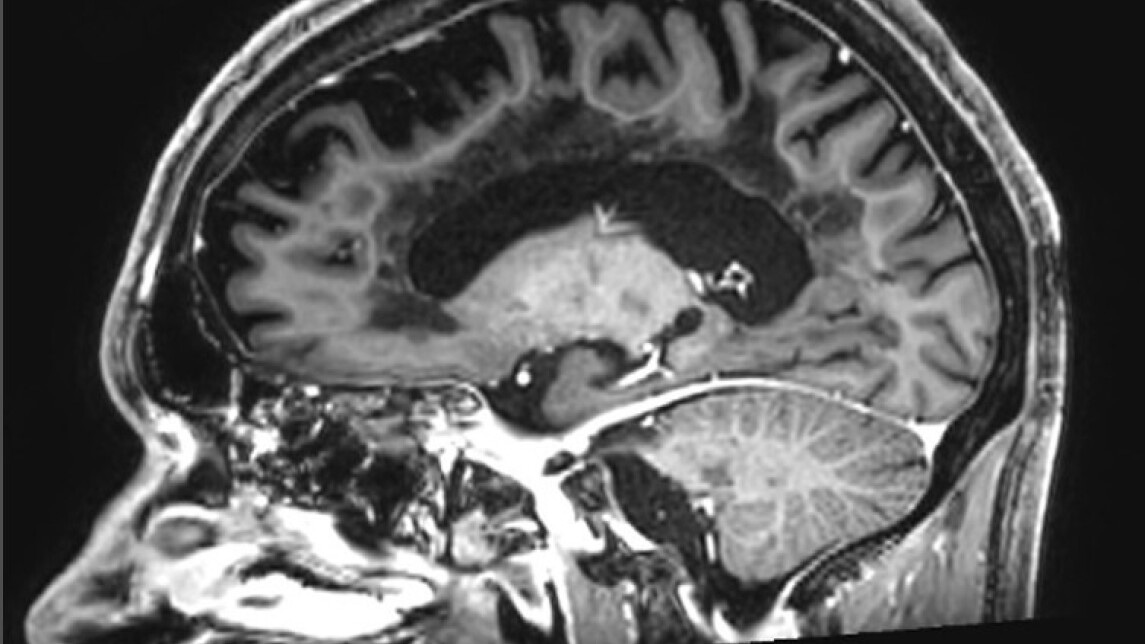

The thickness of the inflammatory cell rim surrounding brain lesions was found to directly correlate with the severity and speed of disease progression. The study, led at the University of Turku in Finland by Professor Laura Airas in collaboration with German and Dutch colleagues, has been published in the prestigious journal Nature Medicine.

The research combined PET imaging data from 114 Finnish MS patients with post-mortem brain tissue analysis from Dutch MS patients. Results show that the wider the inflammatory rim around a brain lesion is, the more aggressively the disease advances.

"When microglial cells form a thick rim around MS lesions, their harmful activity pushes deeper into healthy brain tissue, causing irreversible damage," says Professor Laura Airas.